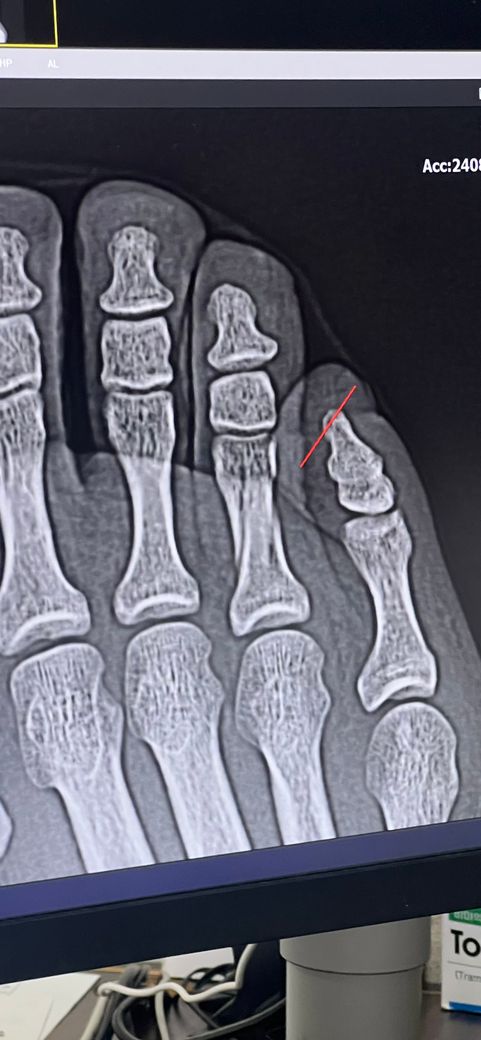

4번째 발가락 골절입니다. 깁스 벗어도 될까요 ?!

현재 3주차 골절 19일째입니다.

현재 병원에서 해주신 깁스와 인터넷에서 본 버디테이핑 중 입니다. 처음 골절 되었던때보다 조금 벌어지긴 했는데 수술은 안해도 될거 같다 하셔서 안하기로 했는데요.

• 1번 째 사진

• 2번 째 사진